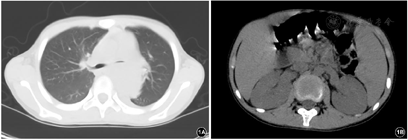

入院后予万古霉素、美罗培南抗感染及支持对症治疗,仍有发热,体温波动于38℃左右,于住院第5天偶诉胸痛、胸闷,可耐受,可自行缓解,复查心脏超声:肺动脉分叉处与降主动脉间见一囊实性回声包块,显示范围约74.8 mm×55.9 mm,内为等回声及无回声。于住院第6天胸痛、胸闷症状加重,伴多汗,每次持续1~20 min不等,前倾位稍缓解,伴呼吸、心率增快,发作时监测血压明显增高,收缩压最高达170 mmHg,含服硝苯地平后可暂时缓解。查体:精神反应欠佳,面色稍苍白,呼吸频率33次/分,三凹征阴性,双肺呼吸音粗,左肺呼吸音减低,可闻及少许痰鸣音,心率101次/分,心音有力,律齐,腋前线第4肋间可闻及2/6级收缩期杂音,足背动脉搏动弱,余未见明显阳性体征。行纵隔增强CT(图2):降主动脉起始段明显缩窄,直径约2.3 mm,狭窄段远端约17 mm处可见降主动脉前缘一膨大造影剂影突出腔外,最大截面约4 5mm×31 mm,上下长度约32 mm,主动脉裂口处宽度约19.4 mm,突出部分周围可见环状软组织密度影包绕,考虑假性动脉瘤形成;复查血常规:WBC 16.17×109/L,Hb 92 g/L,HCT 28.20%,Plt 357×109/L,N 87.0%,L 8.2%,CRP 69.11 mg/L。完善术前检查,于住院第9天全麻低温体外循环下行降主动脉瘤切除、主动脉缩窄切除、人工血管置换术、肺脓肿引流术。术中探查见主动脉峡部缩窄,内径0.3 cm,长约1.2 cm,缩窄段以远2.0 cm处起始主动脉破口,长约3.0 cm,横径1.5 cm,瘤体深入至左肺叶内,5.0 cm×6.0 cm×6.0 cm大小,左肺整体不张实变,张力较高。术中诊断:主动脉缩窄、降主动脉假性动脉瘤、感染性心内膜炎、肺炎并肺脓肿。病理检查示:壁内纤维组织增生及片状出血伴炎症反应,符合假性动脉瘤。术后呼吸机辅助通气,继续予美罗培南+万古霉素抗感染、硝普钠控制血压,体温正常,病情逐渐恢复。于住院第18天,患儿偶诉腹痛,可自行缓解,伴有低热,37.4℃,当天夜间,患儿突然腹痛加重,伴面色苍白、烦躁、意识淡漠。体格检查:T 37.4℃,P 120次/min,R 40次/min,BP右上肢110/65 mmHg。意识模糊,面色及口唇苍白,颈软,无抵抗,呼吸稍促,三凹征阴性,双肺呼吸音粗,未闻及明显湿啰音,心率120次/min,心音有力,律齐。腹韧,右下腹压痛、反跳痛及肌紧张,肝脾肋下未触及,肠鸣音正常,四肢末梢凉,CRT 4 s。急查腹部超声示:右腹部异常回声包块(血肿形成?),急诊腹部增强CT(图3):右肾动脉近段纤细,远端未见显示,右肾实质内可见数条纤细较淡造影剂血管影走行,右肾静脉未见明确显示。右肾受压右移,其内侧及下缘周围可见大片状不均质密度影,大小约90 mm×88 mm×121 mm,内部密度不均,未见明显强化,考虑为巨大血肿。立即全麻下行多学科联合手术(心内科、心外科、普外科、泌尿外科),行腹主动脉造影+肾动脉球囊扩张术+单侧肾切除术+腹膜后血肿清除术。行腹主动脉造影示右肾动脉造影剂外溢。右腹部脐上2 cm长约18 cm横切口,依次打开皮下、腹直肌、腹膜,见腹腔大量凝血块、不凝积血,右下腹膜外巨大血肿,肝脏受压,肠道移向右腹部,右肾呈暗红色,已失活,肾动脉不规则破裂达2/3直径。球囊充液扩张阻断腹主动脉近右肾动脉开口处血流(图4)。清除腹腔及腹膜外凝血块、积血等,暴露肾蒂,游离右肾动静脉、输尿管,7#丝线分别双重结扎、切断右肾动静脉,回抽球囊开放血流,未见出血。同时结扎、切断右侧输尿管,取出失活右肾(图4),充分止血,盐水2000 ml冲洗腹腔。术中诊断:肾动脉破裂;腹膜后血肿。病理诊断:右侧肾脏广泛出血、坏死(图5)。术后体温不稳定,血压仍高,且转氨酶逐渐升高,于住院第33天将万古霉素更换为利奈唑胺(斯沃),后体温逐渐正常,于住院第63天将抗生素降级为舒普深,3 d后停抗生素,观察2 d无症状,临床治愈,于2018年6月29日出院。

根据药敏试验积极抗感染治疗,心外科全麻低温体外循环下行降主动脉瘤切除、主动脉缩窄切除、人工血管置换术、肺脓肿引流术。术后9 d出现腹痛,腹部超声及CT提示巨大血肿,心内科行腹主动脉造影明确部位后给予球囊充液扩张阻断腹主动脉近肾动脉开口处血流,普外科及泌尿外科联合立即行腹膜后血肿清除术及单侧肾切除术,术后继续抗感染及降压治疗。